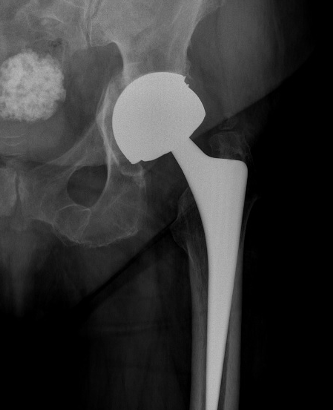

Metal on Metal

Advantage

Large heads

- 30 - 60 mm

- decreases dislocation

- ?improves ROM / function

Disadvantages

1. Increased ion levels

Cobalt and Chromium ions elevated in blood

Creatine cobalt and Creatinine chromium elevated in urine

2. Adverse Local Tissue Reactions

3. High revision rates / Prosthesis recall / Class actions

Australian Joint Registry Revision Rates

|

Metal on Metal > 32 mm |

Metal on Metal < 32 mm |

Metal on Poly | Ceramic on Poly | |

|---|---|---|---|---|

| 3 year | 5.7 | 3.3 | 2.4 | 2,4 |

| 5 year | 11.8 | 4.4 | 3.0 | 2.9 |

| 10 year | 22.6 | 6.8 | 4.5 | 4.0 |

| 15 years | 28.6 | 9.6 | 6.1 | 5.5 |

| 20 years | 32 | 11.9 | 7.5 | 6.8 |